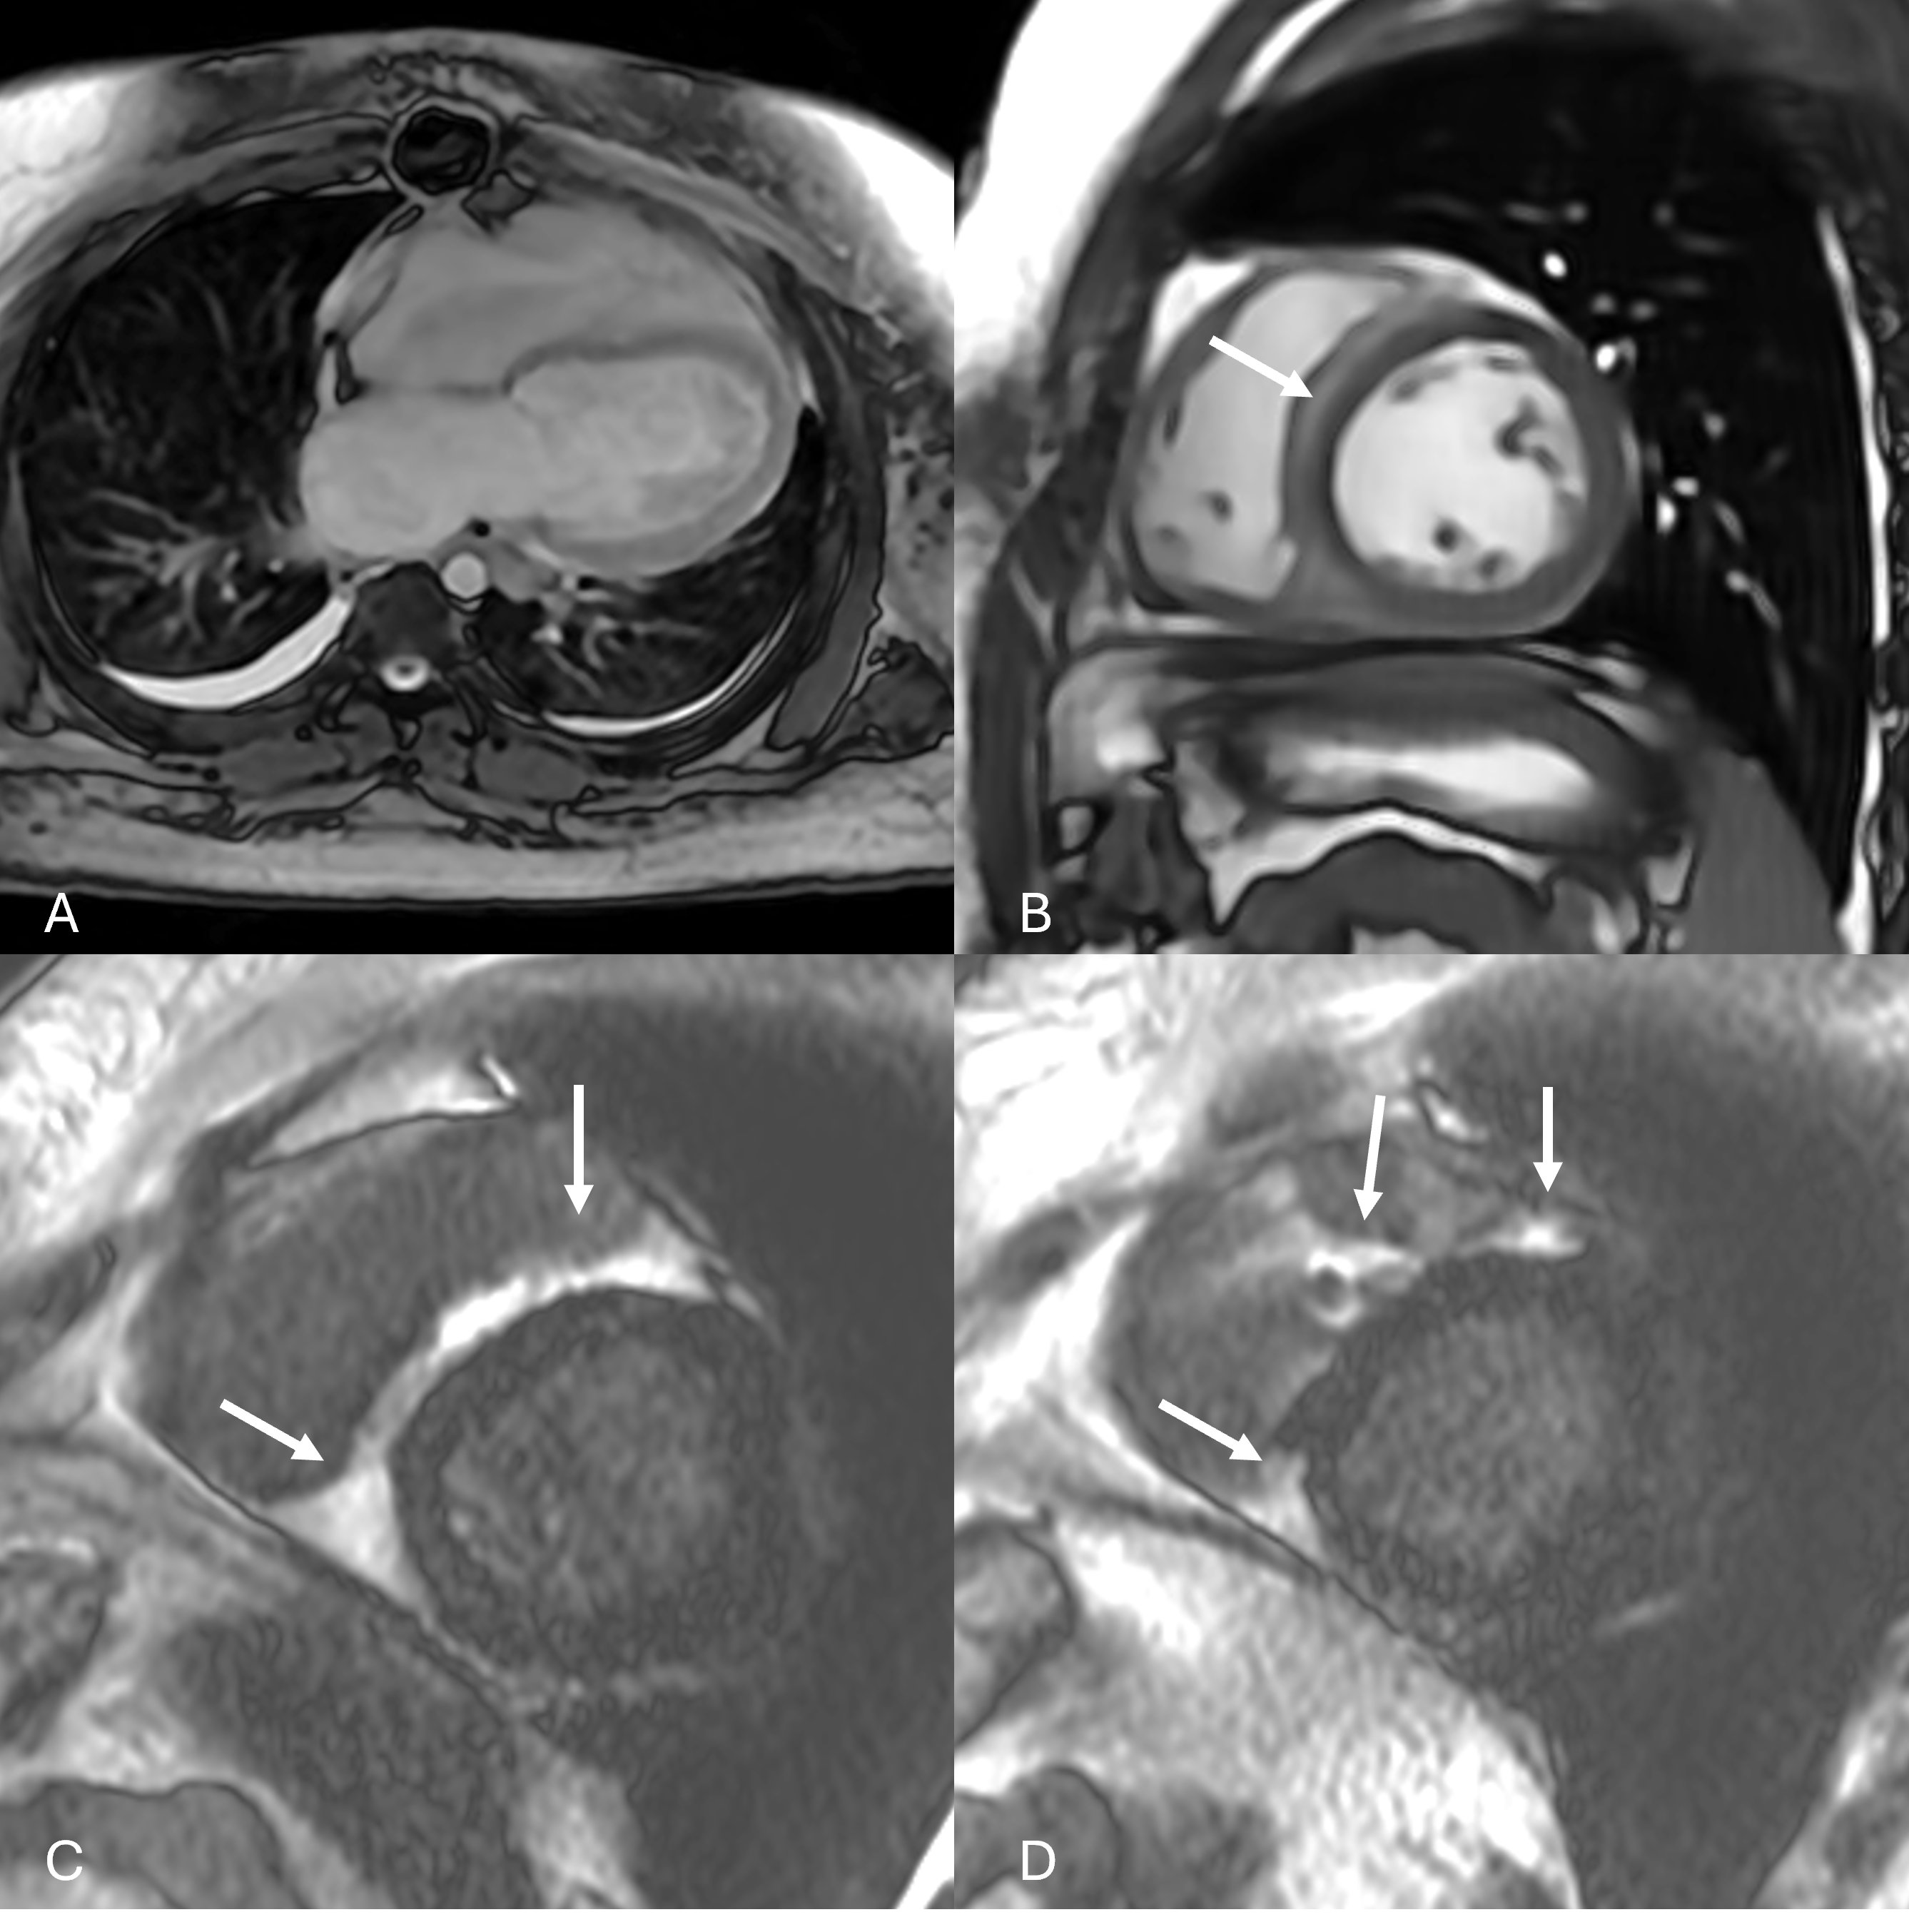

He stabilized and was discharged on Sacubitril/Valsartan and Empagliflozin however 4 weeks later he presented to the ED with concerns for rejection, requiring re-induction with ATG and steroids. A repeat CMR (Fig 2) showed similar dysfunction, ECV, and T2 values as prior and troponin was elevated to 36ng/L.

Figure 2: Panels demonstrating persistent and increased bilateral pleural effusions (A) and abnormal hypodense appearance of myocardium has increased along right ventricular aspect of intraventricular septum (B, arrow) on bSSFP imaging, and late gadolinium enhancement in the right ventricle has improved in the RV septum but may be appearing along the LV free wall subepicardium (C, D, arrows) on LGE imaging.

Figure 2: Panels demonstrating persistent and increased bilateral pleural effusions (A) and abnormal hypodense appearance of myocardium has increased along right ventricular aspect of intraventricular septum (B, arrow) on bSSFP imaging, and late gadolinium enhancement in the right ventricle has improved in the RV septum but may be appearing along the LV free wall subepicardium (C, D, arrows) on LGE imaging.